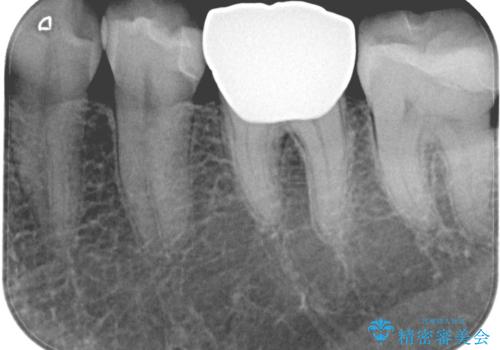

- 銀歯2本の下が虫歯になっていたので、フルジルコニアクラウンとセラミックインレーで治療を行いました。

適合が良い被せ物を入れるために、歯の境としっかり合わせた仮歯を入れ、歯茎の状態を良くしてからシリコンで型取りをしています。